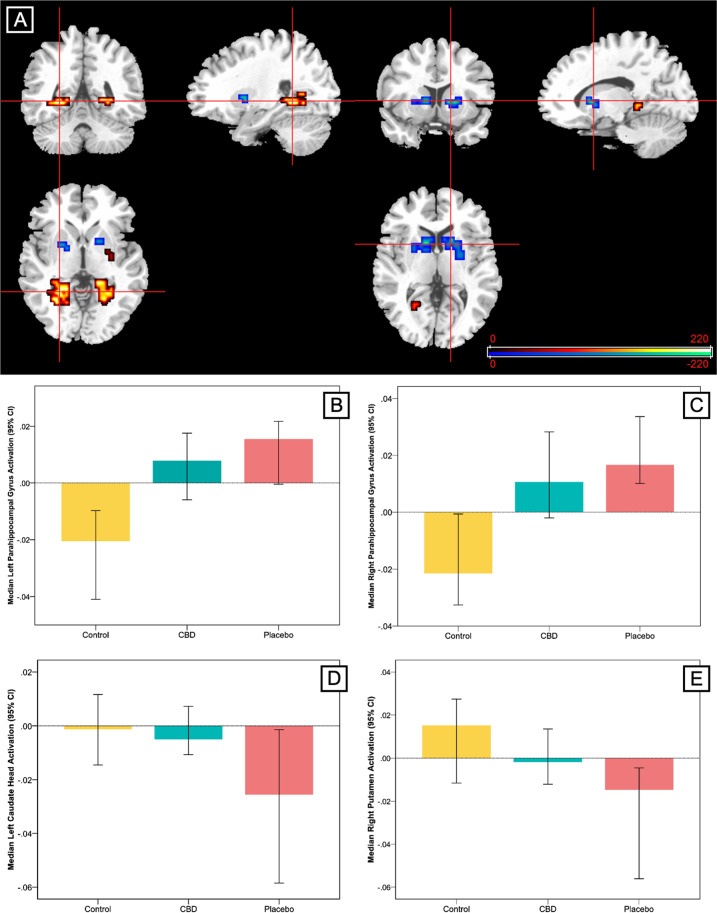

Between-group linear analysis

This analysis identified clusters where the pattern of regional brain activation during fear processing showed a linear relationship across the three groups, such that activation in the CBD group was intermediate to that of the placebo and control groups. A linear relationship was observed in relatively large clusters in the bilateral parahippocampal gyri, with the greatest activation in the group of CHR participants receiving placebo, the lowest in healthy controls and intermediate activation in the CBD group (Table 3 and Fig. 2). These clusters directly overlapped with the parahippocampal clusters differentially engaged by the control and placebo groups in the two-group analyses. The opposite linear pattern was observed in the striatum. Here the highest level of activation was found in healthy controls, the lowest in CHR participants receiving placebo and intermediate activation in the CBD group (Table 3 and Fig. 2). Again, these clusters directly overlapped with the clusters found to be differentially engaged in the placebo vs healthy control group analyses. Removal of the healthy control subject with extreme low task performance (accuracy) scores made no material change to the imaging results (data not shown here).